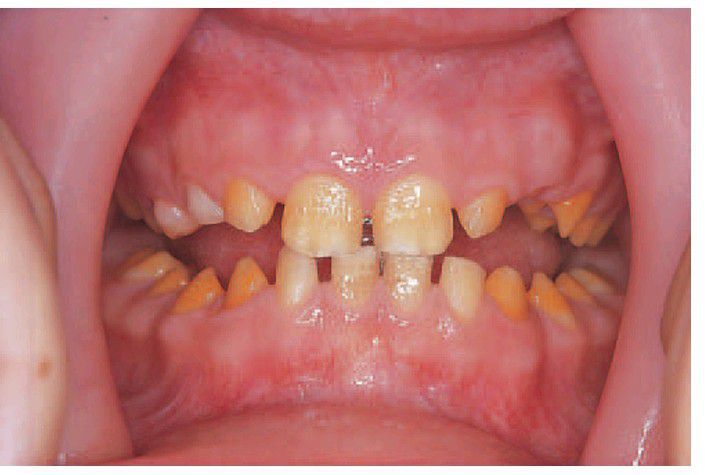

Amelogenesis imperfecta

Amelogenesis imperfecta, hypomaturation type. Tooth morphology is normal but there are opaque white and discoloured patches.